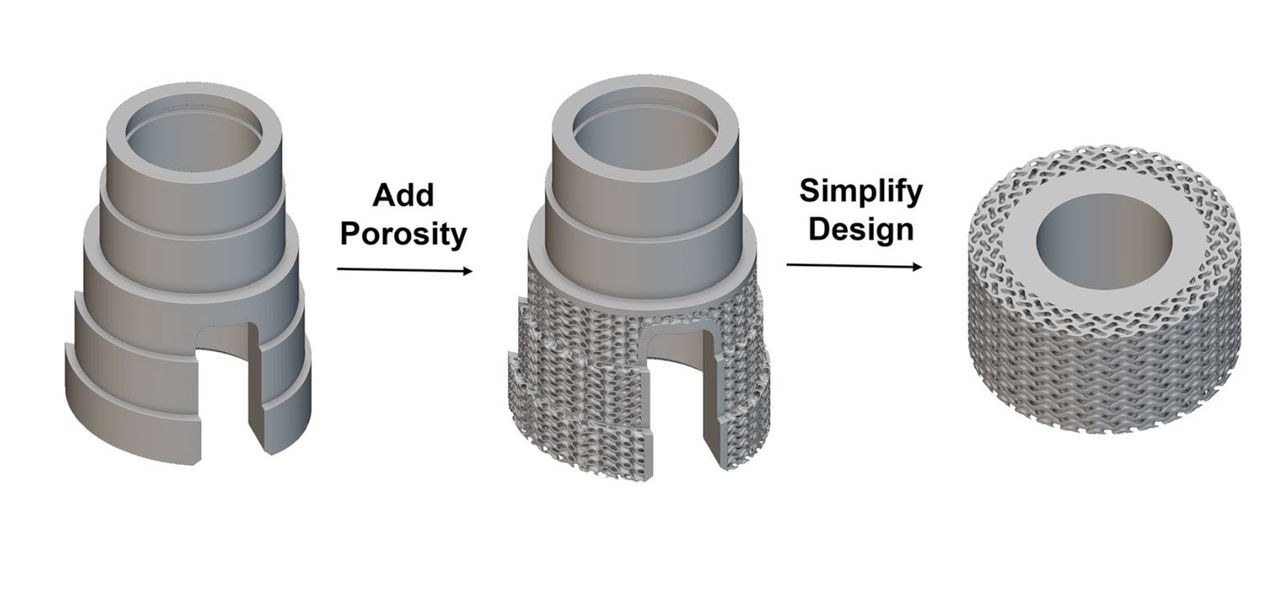

Creating Real Human Bone With 3D Printing

New research at the University of New South Wales has shown a way to 3D print actual human bone. Bone is a highly complex human tissue, as it is both strong and lightweight, mostly due to the detailed natural lattice structure on the interior. Most times a damaged bone can heal itself; a break needs… Continue reading Creating Real Human Bone With 3D Printing

Bioprinters are typically used to 3D print soft tissue, but what about bones?

BioPrinting Breakthrough in Ireland

Researchers at Trinity College in Dublin have worked out a new process for 3D printing live, complex bone structures.